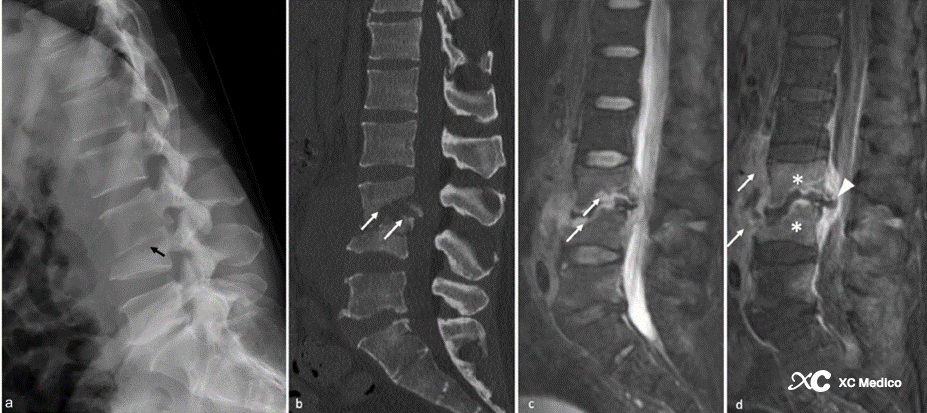

Примечание: (а) рентгенограмма с боковым поясничным позвоночником, показывающая потерю высоты диска L4 -L3 и разрушение верхней конечной пластины L4 (стрелка).

(б) легкий задний скольжение на L3. Разрушение диска L3 - L4 с эрозивными изменениями в соседних конечных пластинах (стрелки).

(C) Магнитно -резонансное изображение (MR), показывающее эрозивные изменения конечных пластин позвонка и аномальный сигнал соседнего костого мозга позвоночного (стрелка). Перевертебральные мягкие ткани заметно являются эдематозными и имеют воспалительные изменения.

(D) Сагиттальный T1 после внутривенного введения контрастного инъекции показывает усиленный сигнал в костном мозге (звездочка), усиленный сигнал в эпидуральном пространстве и мягких тканях с довертебральной. Обратите внимание на отступление центрального канала (стрелка).